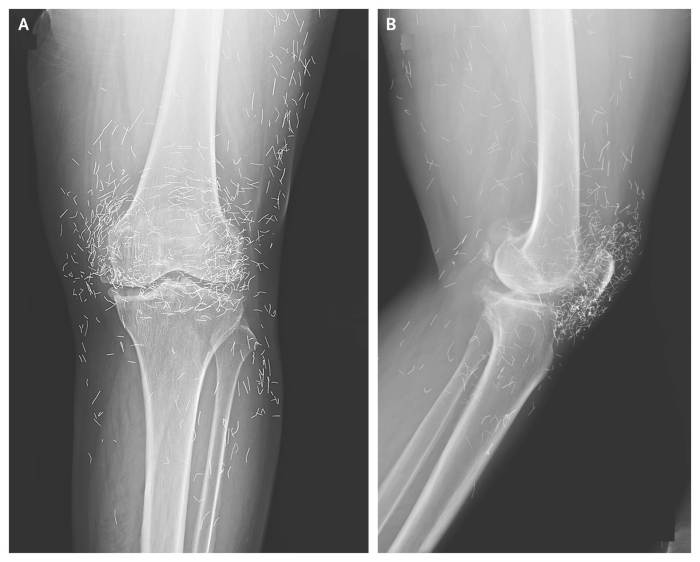

A routine X-ray revealed an unexpected surprise when doctors examined the knees of a 65-year-old woman suffering from severe joint pain.

What they found was nothing short of astonishing — hundreds of tiny gold needles embedded deep in her tissue.

Acupuncture, a traditional therapy widely used in Asia, involves inserting thin needles into specific points on the body in an effort to relieve pain or treat illness. In this case, however, doctors say the gold needles were left behind intentionally as part of her treatment plan, designed to deliver continuous stimulation to the affected area.

There are other complications as well. Needles lodged in tissue can interfere with medical imaging. “They can obscure parts of the anatomy on an X-ray,” Guermazi noted. Even more alarming, patients with metal fragments in their bodies should never undergo an MRI, as the magnetic force could cause the needles to move — potentially puncturing blood vessels and causing life-threatening damage.

A X-ray of the patient’s knee showing acupuncture needles embedded in the tissue, Photo Credit: Reddit

As for the South Korean woman, her case was recently documented in the New England Journal of Medicine. While the needles may have been intended to help, her X-rays tell a cautionary tale about the potential risks of extreme alternative therapies.